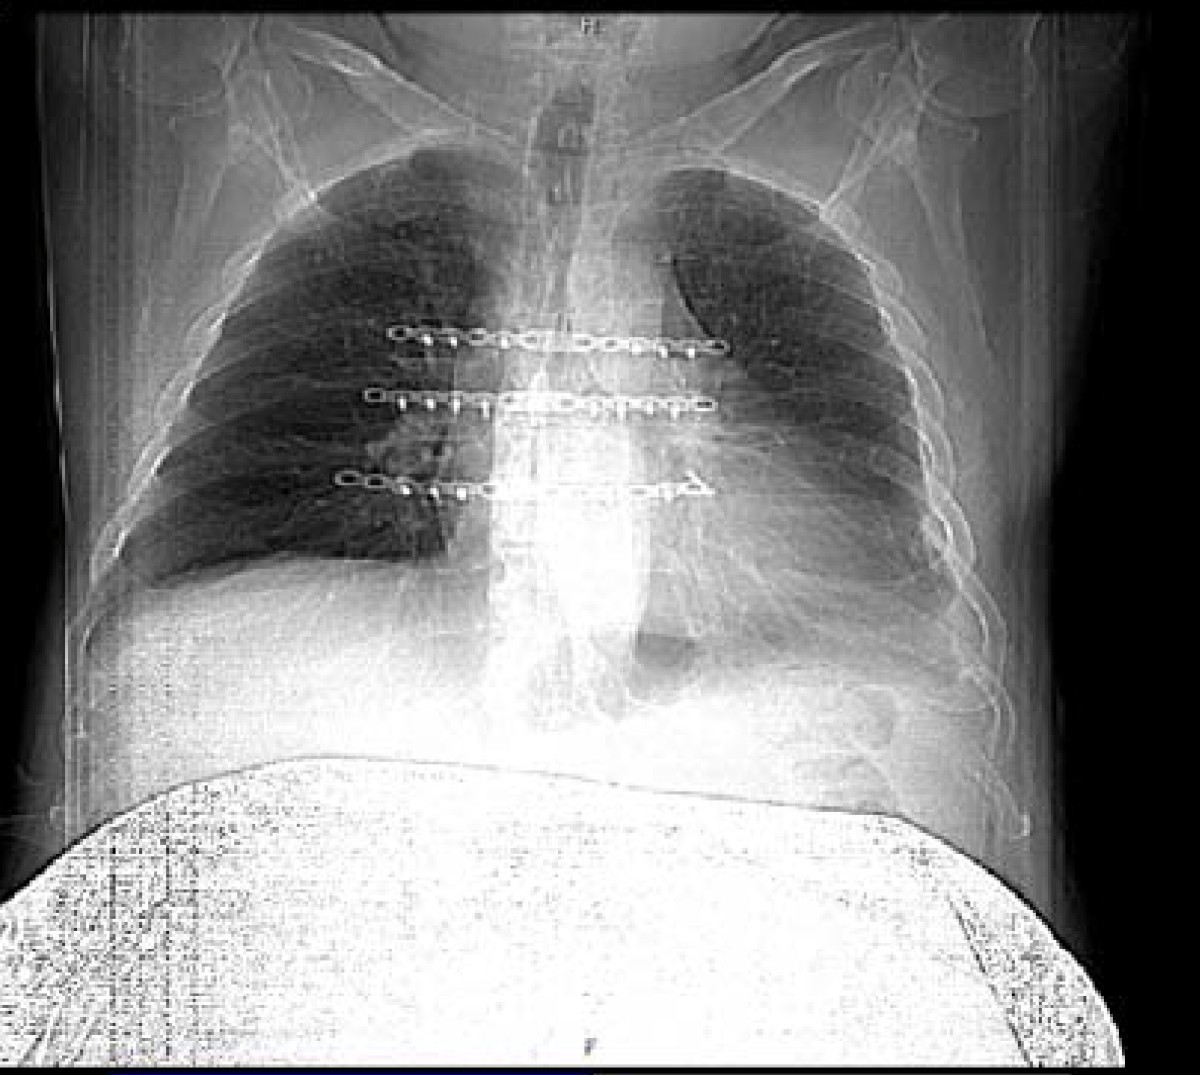

• Fracture Of The Sternum X-ray - Stock Image 6805

• Chest Radiograph Posterior

• Normal Frontal Chest X